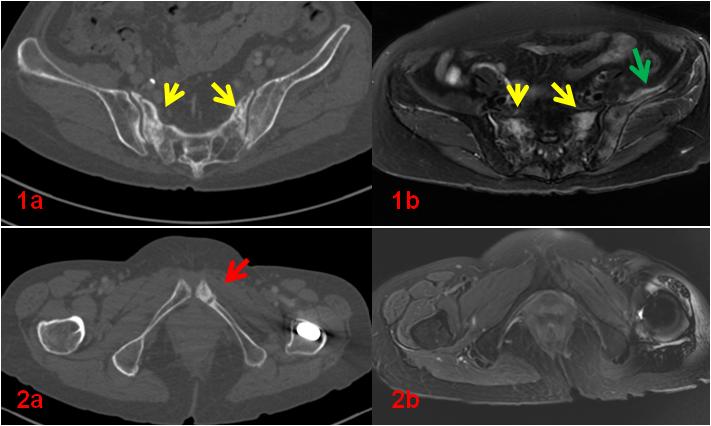

老年女性,1年前因直腸惡性腫瘤于外院行放射治療,此次常規(guī)復查平掃CT示骶骨及左側(cè)恥骨密度不均勻,左側(cè)恥骨骨質(zhì)斷裂;平掃MR示雙側(cè)骶骨翼、左側(cè)髂骨及左側(cè)恥骨異常信號(圖1、2);為進一步明確診斷行全身骨顯像ECT檢查(圖3)。

圖1、2初診CT、MR影像。CT示骶骨密度不均勻增高(1a,黃箭),同部位MR顯示壓脂信號增高(1b,黃箭),同時顯示左側(cè)髂骨及周圍軟組織壓脂信號增高(1b,綠箭);左側(cè)恥骨骨質(zhì)斷裂(2a,紅箭)。

復查CT(圖4、5)對比前片(圖1a、2a)。前片所示骶骨密度不均勻增高(1a,黃箭),本次明顯恢復(4,黃箭),左側(cè)恥骨骨質(zhì)斷裂(2a,紅箭),本次基本消失(5,紅箭)。